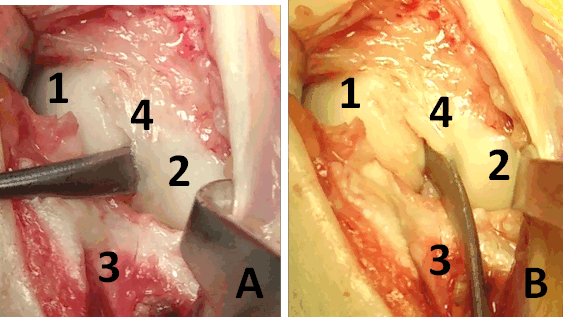

Описание техники оперативного лечения. Операция проводилась под региональным обескровливанием при помощи пневматического жгута. В положении пациентки на спине рука располагалась на приставном столике. Выполнялся тыльный продольный доступ в проекции лучезапястного сустава. Остро и тупо препарировались мягкие ткани с визуализацией сухожилий разгибателей пальцев кисти. Удерживатель сухожилий разгибателей рассекался в третьем компартменте, после чего сухожилия разгибателей пальцев кисти разводились в разные стороны. Капсула сустава рассекалась Т-образно. В полости лучезапястного сустава визуализировалось избыточное содержание синовиальной жидкости, разрастание синовиальной оболочки сустава, отрыв ладьевидно-полулунной связки (рис. 3). При ревизии трехгранного комплекса патологических изменений выявлено не было. Осуществлялось проведение биодеградируемого пина 1,5 мм через ладьевидно-полулунное сочленение по оси полулунной кости для сопоставления костей проксимального ряда запястья. Контроль положения ладьевидной и полулунной костей был исследован при помощи электронно-оптического преобразователя (далее ЭОП). В область дефекта ладьевидно –полулунной связки в проксимальный полюс ладьевидной кости устанавливался биодеградируемый якорный фиксатор с последующим восстановлением целостности поврежденной тыльной порции ладьевидно-полулунной связки (рис. 4). Восстановление осуществлялось за счет формирования дубликатуры культи связки и её трансоссальной фиксации к полулунной кости. В дальнейшем осуществлялась пластика капсулы лучезапястного сустава. Восстанавливалось положение сухожилий разгибателей пальцев правой кисти, осуществлялась пластика удерживателя сухожилий.

На фотографии (рис. 4) во время операции видна восстановленная ладьевидно-полулунная связка. Послойно накладывались швы на рану, асептическая повязка, гипсовая иммобилизация лучезапястного сустава.

Рис. 3. Фотография операционной раны. А, B: 1 – ладьевидная кость, 2 – полулунная кость, 3 – лучевая кость, 4 – полулунно-ладьевидная связка.

Между ладьевидной и полулунной костями в дефект установлен элеватор

Рис. 4. Реинсерция ладьевидно-полулунной связки: 1 – ладьевидная кость, 2 – полулунная кость, 3 – лучевая кость, 4 – полулунно-ладьевидная связка